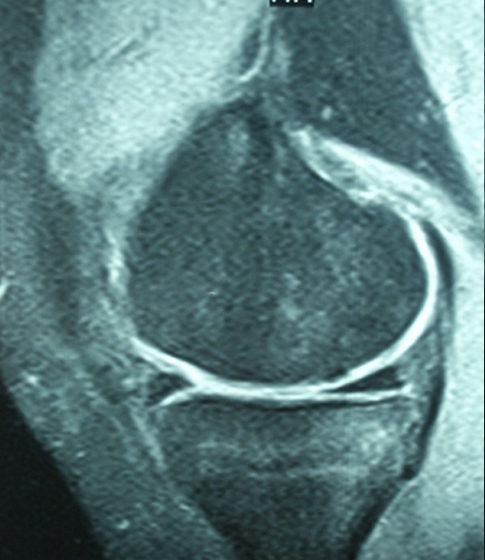

18 yaşında erkek hasta, profesyonel basketbol oyuncusu.

Uzun süredir devam eden diz ağrıları, maç sırasında gelişen burkulma ile artmış. Dizde şişme, ağrı ve basamama şikayetleri ile başvurdu. MR tetkikinde eklem hattında kıkırdak ve kemik içeren büyük bir eklem faresinin serbestleştiği görüldü (Gr 3 Osteochondritis Dissecans)

Hastanın ayrışmakta olan kıkırdak hattı kendi dizinin diğer alanlarından alınan kemikli kıkırdak tüpleri ile artroskopik olarak tespit edildi. (Mozaikplasty Plug Tespiti) Böylece hem ayrışmakta olan kıkırdak tespit edildi hem de ayrışma bölgesi taze kemik ve sitokinlerle tekrar kaynamaya zorlandı.

Hastanın ameliyattan sonraki birinci yıl MR tetkiklerinde ayrışmanın tamamen iyileştiği gözlendi.